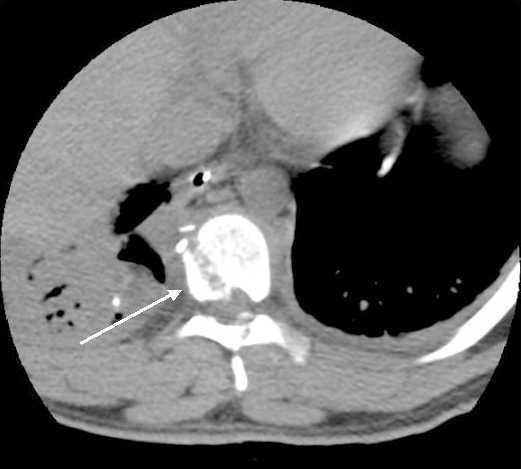

Se trata de un paciente de 23 años que sufre agresión por arma de fuego. Presenta orificio de entrada en hemitórax derecho en línea medioclavicular a la altura de séptimo espacio intercostal de unos 3-5 mm de diámetro y no se localiza orificio de salida. Clínicamente el paciente presentaba insuficiencia respiratoria y un nivel medular sensitivo-motor D6-D7 compatible con sección medular completa a dicho nivel. El paciente se sometió a toracotomía posterolateral quirúrgica por lesión de lóbulos pulmonares medio e inferior derechos y se localizó el proyectil en zona subcutánea de hemitórax izquierdo. Entre las pruebas de imagen realizadas destaca una tomografía axial computarizada torácica con hemotórax derecho masivo e imagen de trayecto oblicuo por proyectil a nivel D8 con salida por el arco posterior (flecha).